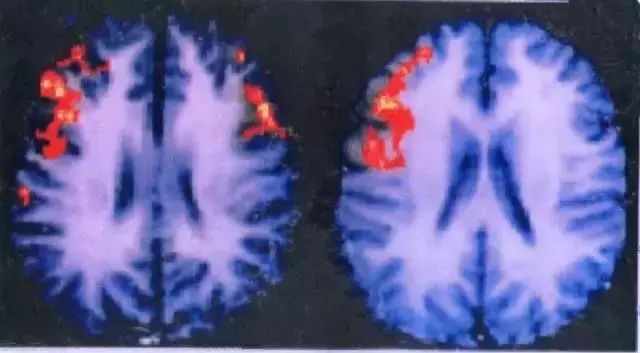

(左边是女生的脑,右边是男生的脑)

在一次TED演讲中,心理学博士洪兰教授解读了男女大脑差异:男生说话时,单侧脑区被激活,女生说话时两侧脑区被激活,这个功能上的差异来自于男女大脑结构上的不同。

两个脑半球中间,有数百万以上的纤维束联结,这些纤维束被称为胼胝体,它就像是一个连接两个脑半球的桥。桥越宽,两侧半脑的信息传输速度就越快。

女生胼胝体比男生厚很多。情绪在右脑、语言在左脑,因此女生更擅长她的情绪用语言的方式表达出来。所以我们经常看到夫妻吵架,丈夫讲1个字,妻子讲10个字。